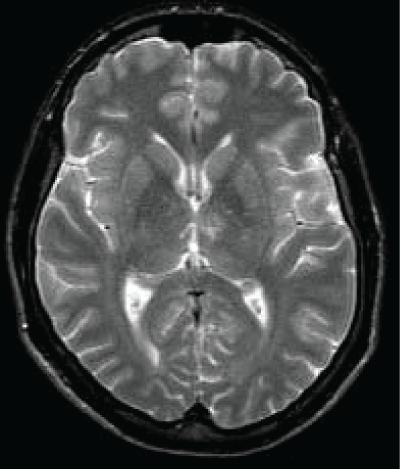

A 45 years old Caucasian male was admitted to our Neurological Clinic for a sudden onset of visual impairment and pure horizontal diplopia, disequilibrium and left lateropulsion. While he was coming to hospital he noted also a speech disorder (mainly referred as word-finding difficulties, reduced fluency, denomination and writing disorders). At admission cerebral CT and angio-CT was performed but no lesions were seen, neither vessels abnormalities. During hospitalization antiplatelet therapy was started. Patient performed screening vascular examination including echocardiography carotid Doppler and thrombophylic screening tests. Soon dizziness and visual disorder ameliorated but then he showed palipsychism (which corresponds to an overlap of sequential cognitive processes in two or more domains); patient also showed severe perseverative behavior with increased sensitivity to interference, anterograde memory retrieval deficit with memory loss and produced a decreased and invalid-output speech, characterized by unpredictable topic shifts, with grammatically correct phrases, sometimes he accused naming difficulties and apathy with affective flatness. Moreover he accused some kind of stiffness on both his upper arms. Neuropsychological tests were performed showing preservation in performing automatic series and executive functions, and a "transcortical sensitive-aphasia-like speech disorder". After a few days cerebral magnetic resonance was performed, it showed a thalamic ischemia in the paramedian left thalamic nuclei territory (Figure 1 and Figure 2); as a result of a possible cardioembolic stroke.

As we said the fluid-attenuated inversion recovery (FLAIR) and T2 MRI revealed a hyperintense lesion (hypointense in T1 sequences) compatible with a left paramedian thalamic infarction in a patient with onset of confusion, confabulation, and memory impairment (Figure 3). Patient was discharged at home but he felt not to be confident to live alone anymore.